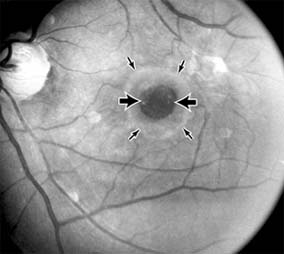

MACULAR HOLE

A macular hole is a partial or full-thickness absence of the sensory retina in the macula. This disorder occurs most often in elderly women and is associated with elevated plasma fibrinogen levels. The typical finding on biomicroscopy of the symptomatic eye is a full-thickness, round or oval, sharply defined hole measuring one-third disk diameter in the center of the macula, which may be surrounded by a ring detachment of the sensory retina (Figure 10-11). With a full-thickness macular hole, visual acuity is impaired and metamorphopsia, as well as a central scotoma, are present on the Amsler grid. An operculum of retinal tissue may overlie the macular hole. Tangential traction from epiretinal vitreous cortex plays an important role in the pathogenesis of macular hole. Early stages of macular hole formation, such as a deep foveal yellow spot or ring, may be reversible as the posterior vitreous cortex spontaneously separates from the retina. Therapy for macular hole disease involves reattaching and potentially restoring function to the retina overlying the cuff of subretinal fluid surrounding the hole. While the anatomic results of vitrectomy surgery to close macular holes are encouraging, the clinical benefits are still under study.

Figure 10-11

Figure 10-11: Macular hole (large arrows) with surrounding sensory retinal detachment (small arrows).